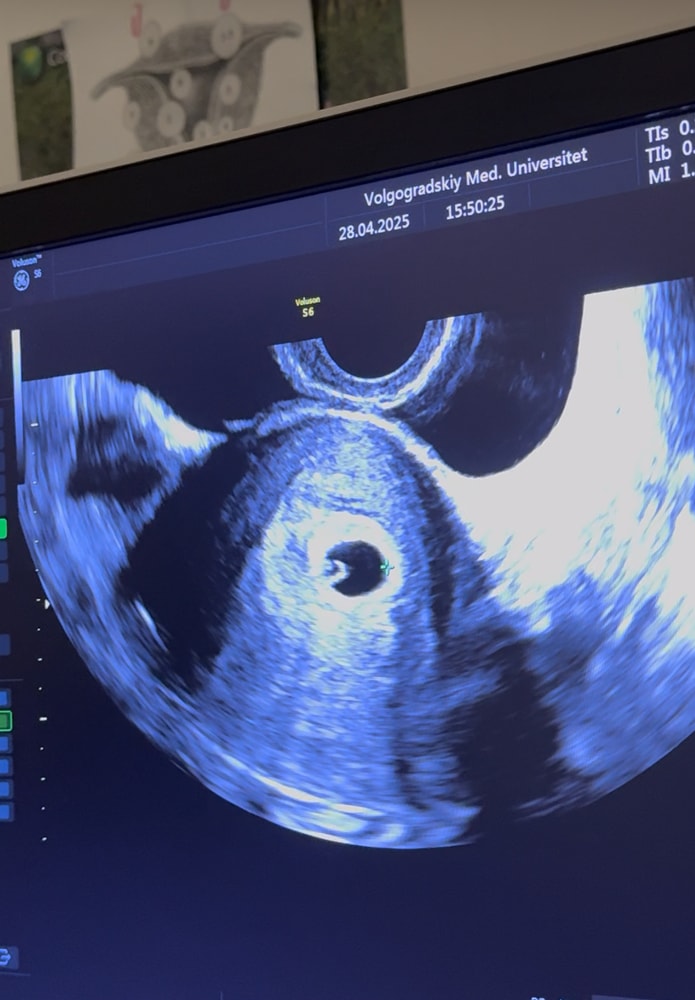

Всё о нашей беременностиНа первом узи на 21дпп, написано пя и жм.

Пересматривая видео с узи, где ре говорит про вот он ваш маленький бриллиантик, я так понимаю что был уже малюсенький эмбриончик, верно же я не ошибаюсь?фото прикрепляю.

Очень переживаю, пока жду следующее узи🤍